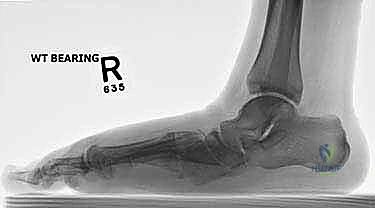

- الأشعة السينية أثناء الوقوف (Weight-bearing X-rays): وهي أهم أداة تشخيصية. الأشعة العادية والسرير فارغ لا تظهر المشكلة الحقيقية؛ يجب التقاط الأشعة والمريض يقف ليتحمل وزن الجسم، مما يظهر الانهيار الفعلي للمفاصل وتضيق المسافات بين العظام.

تعمل هذه العظام معاً كـ "ممتص للصدمات" أثناء المشي والجري. المفاصل التي تربط هذه العظام (مثل مفصل تارصو-ميتاتارسال أو مفصل ليزفرانك Lisfranc joint) هي مفاصل ذات حركة محدودة جداً، ولكنها حيوية لاستقرار القدم. عندما تتآكل الغضاريف التي تغطي نهايات هذه العظام، تبدأ العظام بالاحتكاك ببعضها البعض، مما يولد ألماً مبرحاً ويؤدي إلى انهيار قوس القدم.

- العيوب الخلقية أو التشوهات المكتسبة: مثل القدم المسطحة الشديدة (Severe Flatfoot) التي تتصلب مع مرور الوقت وتصبح مؤلمة للغاية.